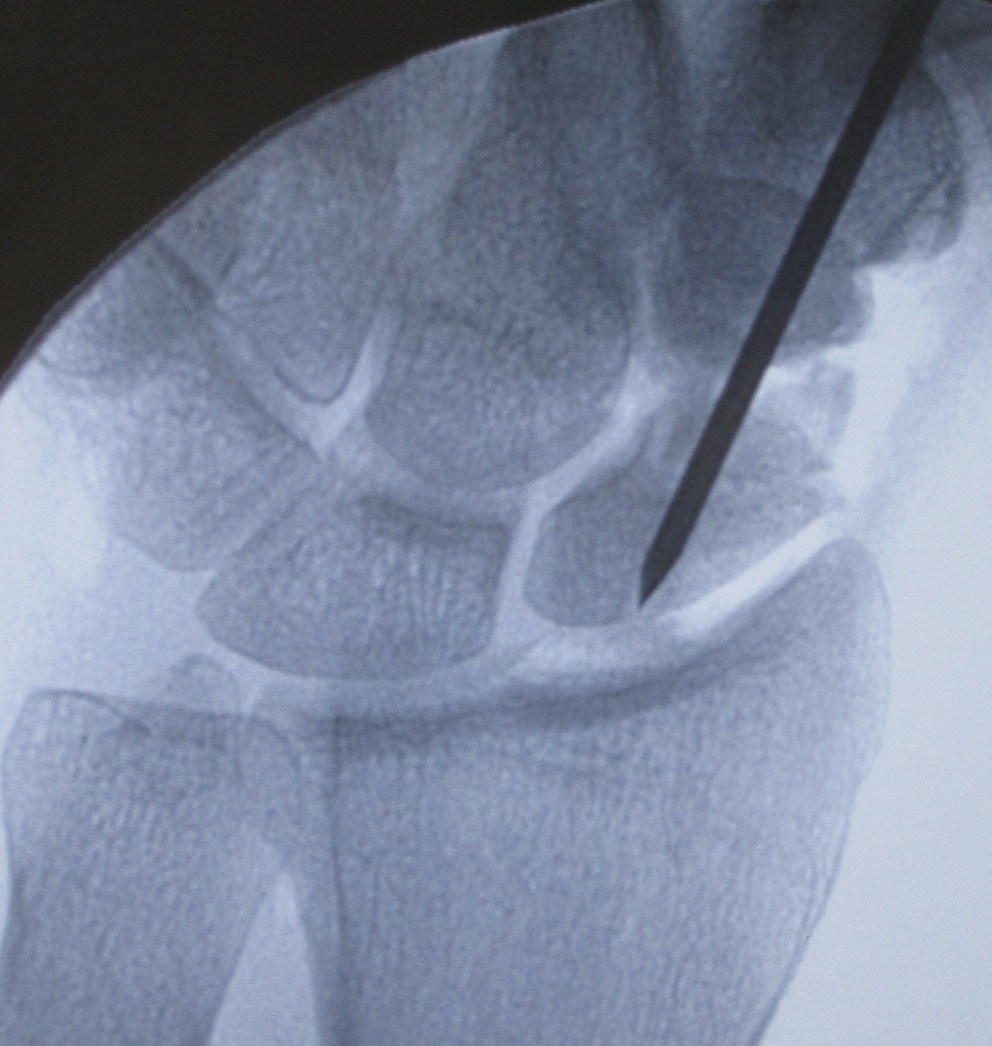

- fix with K wire

- place cannulated screw

Place bone graft

- reduce deformity if necessary